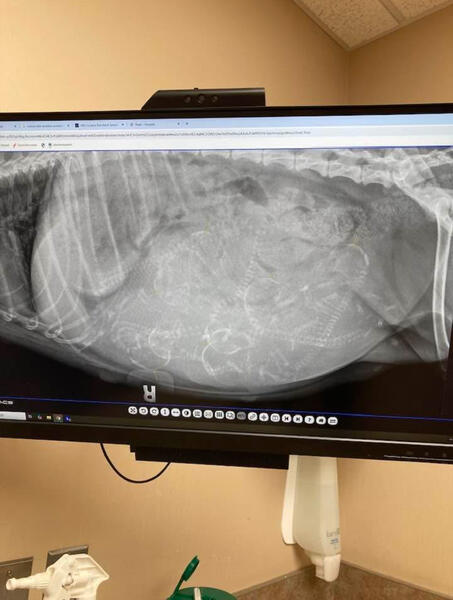

My beloved golden doodle, Molly, is expecting a litter of puppies, but weve just received devastating news from her veterinarian due to complications with her pregnancy, Molly will need an emergency Cesarean section (C-section) to safely deliver the puppies. Without this life-saving surgery, both Molly and her unborn puppies are at risk of dying.

The cost of the procedure is $3,500, which includes the surgical operation, post-op care, and the immediate medical support needed for the puppies once they are delivered. As much as I wish I could cover it all on my own, the expense is more than I can manage alone in this short timeframe.